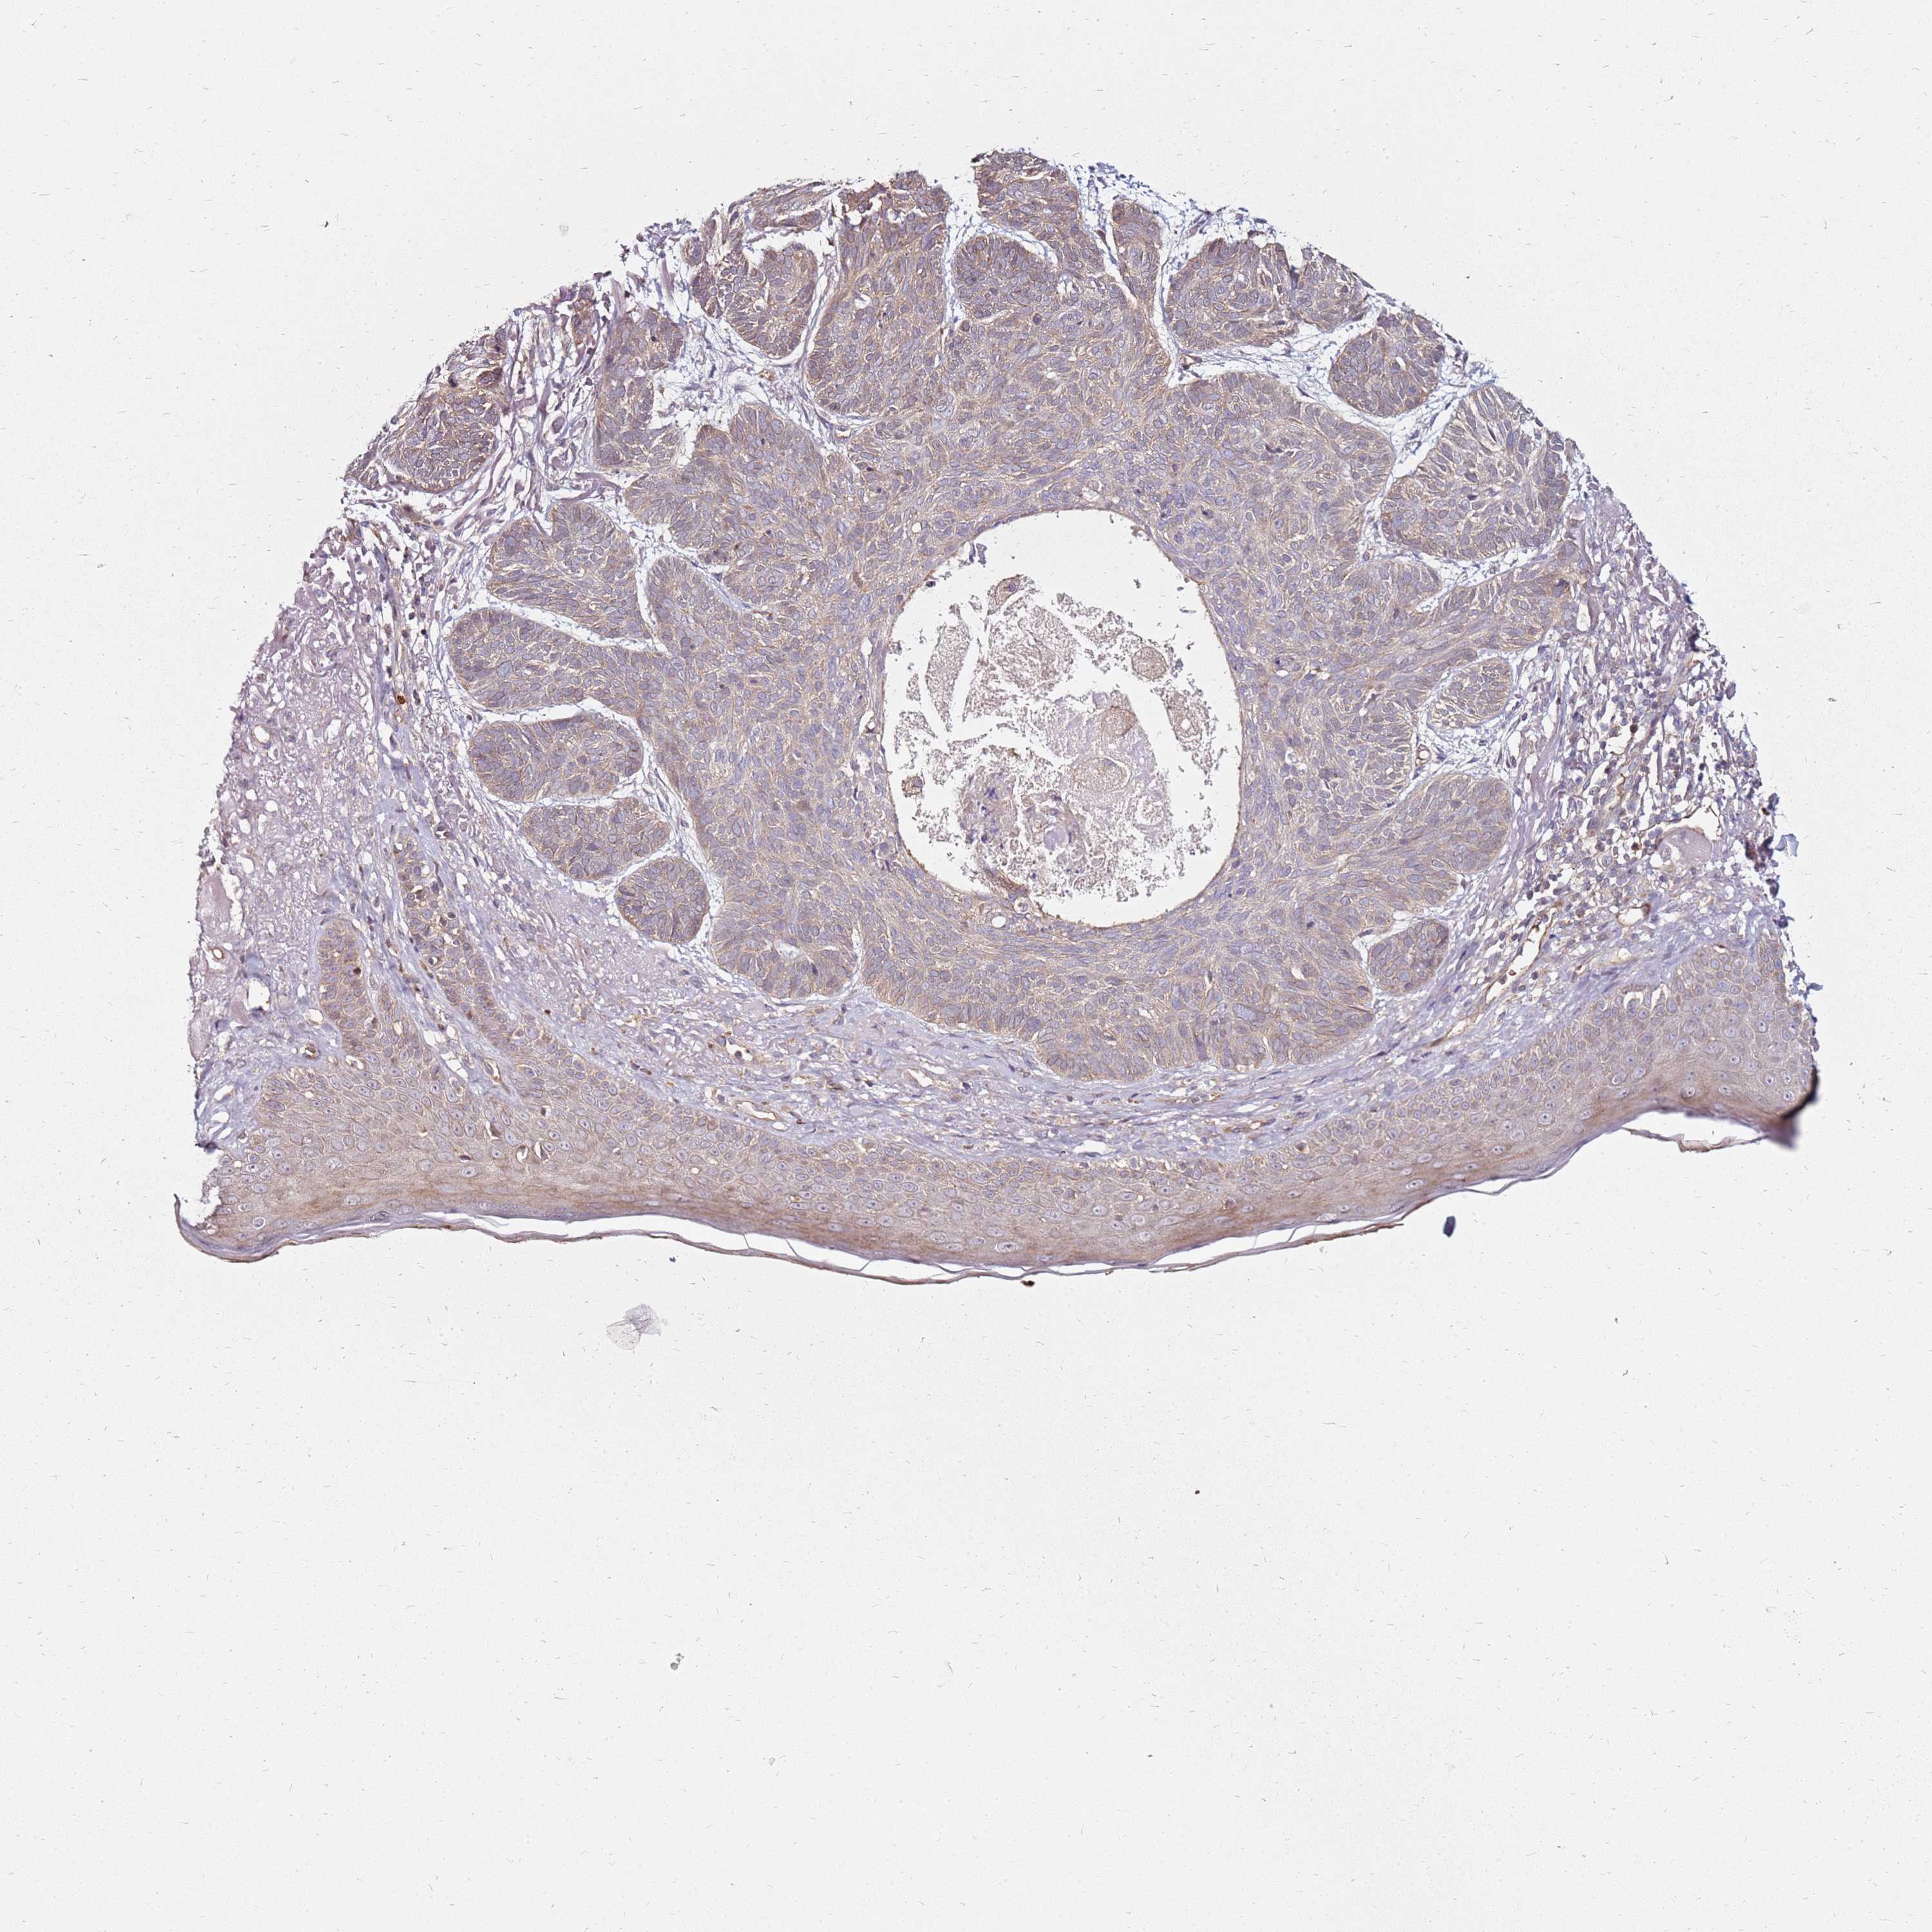

SKIN CANCER - Protein expressioni

A mouse-over function shows sample information and annotation data. Click on an image to view it in a full screen mode. Samples can be filtered based on level of antibody staining by selecting one or several of the following categories: high, medium, low and not detected. The assay and annotation is described here.

Each image is clickable and will lead to virtual microscopy that enables deeper exploration of all samples and also displays staining intensity scores, fraction scores and subcellular localization as well as patient and tissue information for each sample.

Antibody HPA045781

Squamous cell carcinoma, NOS